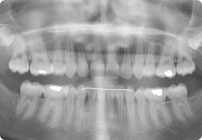

Caso: 11 años

Adolescente: Clase II

Mordida Cruzada Posterior

Sin extracción

Sin uso de expansores

6 alambres superiores

5 alambres inferiores

Sin uso de elásticos

Retenedores: Interior Fijo de TMA y Hawley en superior

Tiempo de tratamiento: 14 Visitas